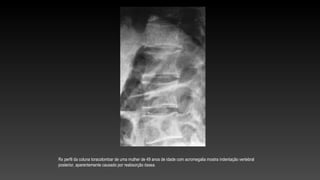

Rx perfil da coluna toracolombar de uma mulher de 49 anos de idade com acromegalia mostra indentação vertebral

posterior, aparentemente causado por reabsorção óssea.